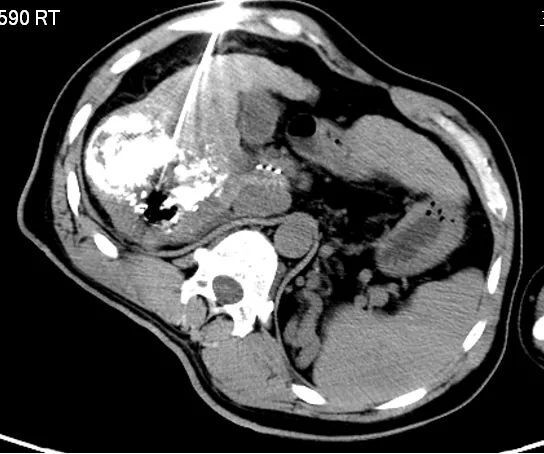

中晚期肝癌的介入联合消融治疗 中晚期肝癌,介入消融快速减瘤,效果

图片尺寸1920x1440